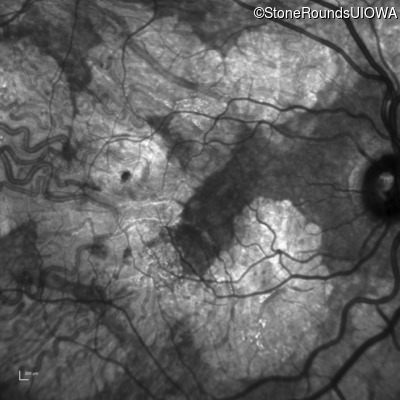

Infrared Fundus Photograph - Right - 20/40 -2

Exemplar

Infrared Fundus Photograph - Left - 20/40 +1